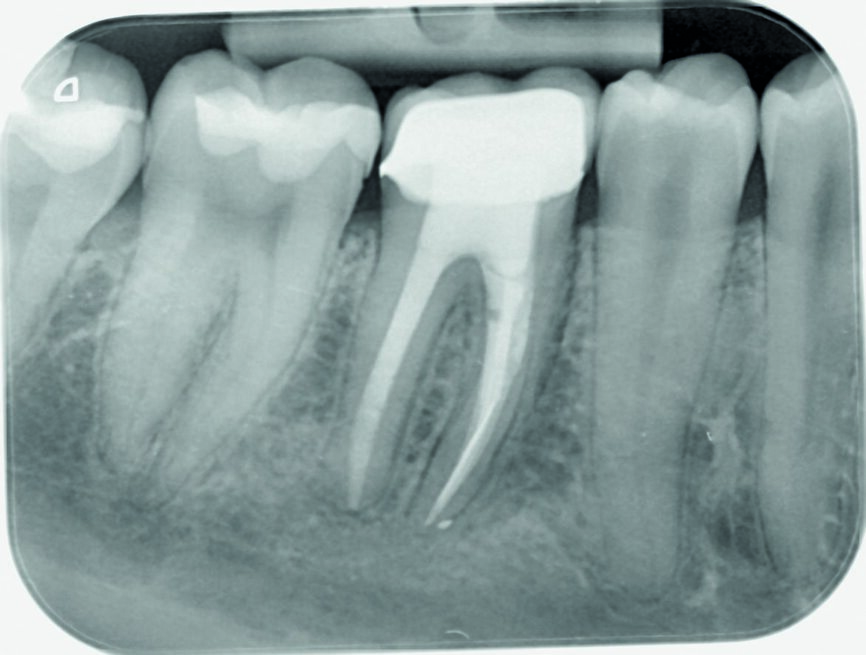

The patient was recalled after one month (Fig. 6), three months (Fig. 7) and six months (Fig. 8) for clinical and radiographic follow-up. Clinical examination of tooth #46 found it to be functional without sensitivity to percussion or palpation. The tooth showed normal physiological mobility and no periodontal pockets on probing. The periapical radiographs showed satisfactory periapical bone density with no sign of periapical radiolucencies and no further progression of the resorptive process around the distal apical zone. The treatment was definitively finished with a crown. After one year, the patient was recalled again, and the tooth was found to be symptom-free. No percussion sensitivity was observed. The periapical radiograph showed a satisfactory image (Fig. 9)

Fig. 6: Control radiograph after one month

Fig. 7: Control radiograph after three months

Fig. 8: Control radiograph after six months

Fig. 9: Control radiograph after one year